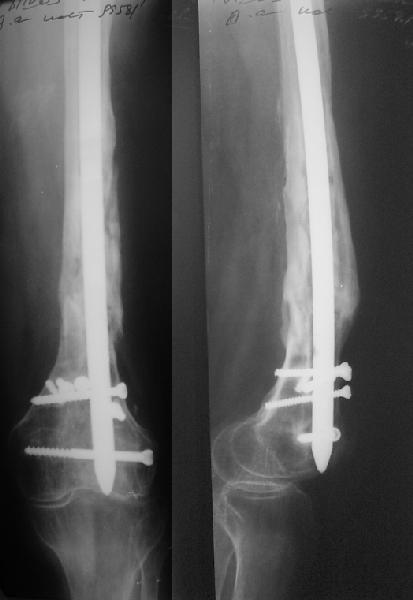

В 2002 г. была у нас больная с ложным суставом бедра и остеомиелитом (как оказалось), после удаления пластины. Гвоздь с блокированием.

Потекло через месяц - открылось 2 свища по старому рубцу от давно удаленной пластины. На фоне гноя раза три завинчивал обратно винты, которые вылезали латерально, прямо через свищ. Потом таки провел дополнительно винты мимо гвоздя, и убрал вверху статический винт. Острый гнойный процесс стих, свищи мыла она дома дважды в день водным хлоргексидином, ходила с возрастающей нагрузкой, а к 10 мес. и свищи закрылись, и срослось. Итоговые снимки от 18 апреля 2003 г. прилагаю.